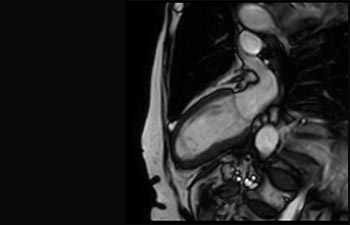

Sehen Sie selbst, was die ersten Nutzer von Ingenia Prodiva 1.5T über ihre Erfahrungen mit dem System und dessen Auswirkung auf ihre radiologische Praxis berichten.